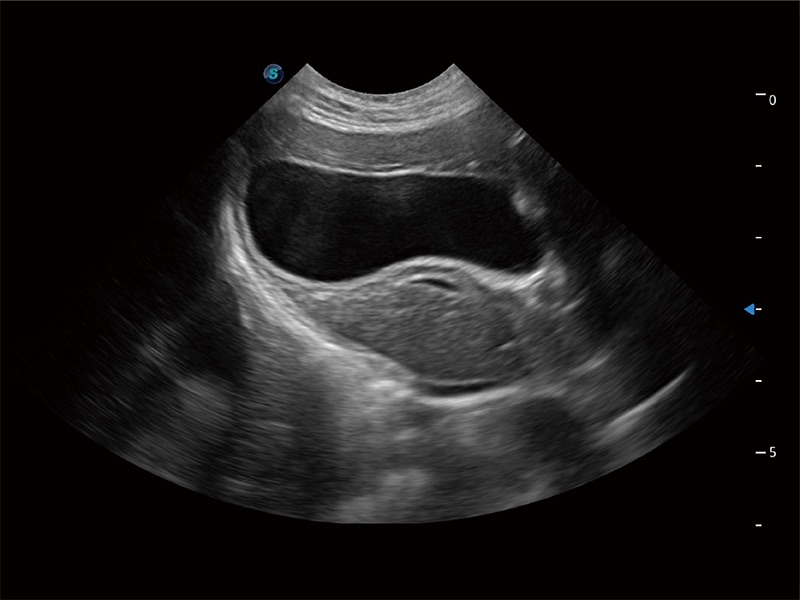

一键自动识别膀胱壁及自动测量膀胱容积,不受膀胱形状和大小的限制,帮助医生快速精准获得测量的数据。

ProPet 80 专为动物医生设计,对不同的动物体型和生理结构作出了针对性的优化。通过动物影像专用软件,可满足个性化的应用需求,帮助动物医生获得更精确的诊断数据。

ProPet 80 全新的动物超声智能软件和丰富的探头群,为动物医生提供了高清晰度和精细分辨率的图像,无论在宠物、马科、畜牧还是实验室动物等应用中都可以轻松应对,为您的日常工作带来满意的体验。